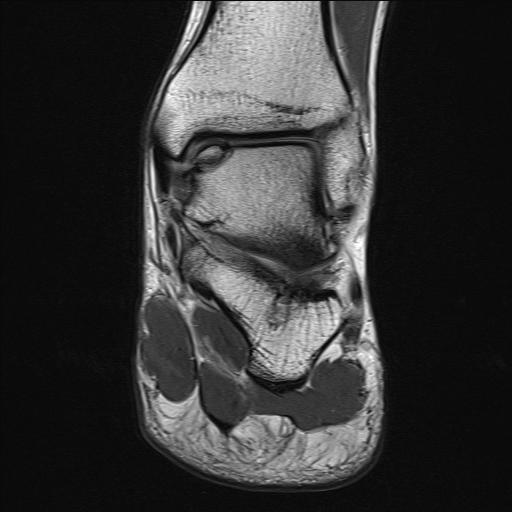

MRI

Stable lesion (Stage I) - cartilage intact, no synovial fluid under lesion

Unstable lesions (Stage II or III) - cartilage breach, synovial fluid under lesion

Displaced lesion with resultant osteochondral defect

Stable lesion with intact cartilage and no synovial fluid under lesion

Stage III completely detached but not displaced